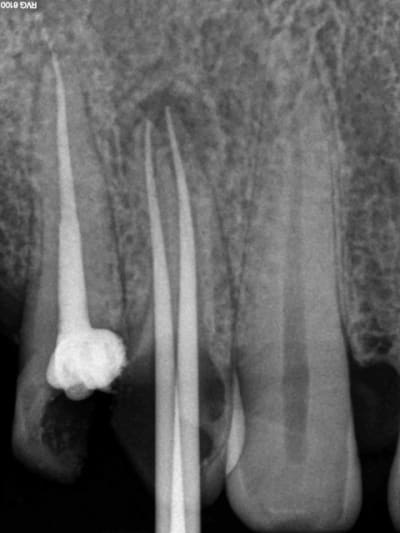

Aujourd'hui patient en urgence ca tombe bien pour une fois synchro avec un lapin.

45 mn de turbinage intensif 2 endos + 2 SC 33; On cote comment les radios ?

Z6, SC 20, Z3,Z3, SC20, Z3, Z3, SC 33, Z3, SC 33, Z3 ?